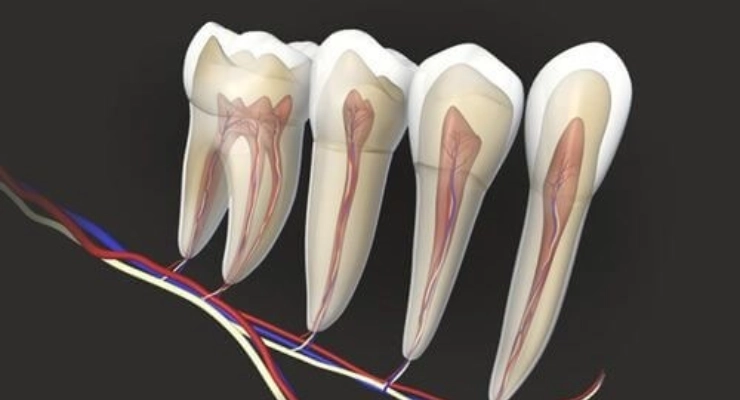

Chronic tooth pulp inflammation (chronic pulpitis) is a long‑standing condition that affects the dental pulp (the tooth nerve) gradually over time. The pulp inside the tooth becomes inflamed due to deep dental caries, a tooth fracture, or neglecting treatment of earlier infections. This form of pulp inflammation often causes milder symptoms than acute pulpitis, but it is more serious because it can persist for a long time and may progress silently without obvious pain in its early stages.Over time, chronic pulpitis can lead to complete damage of the pulp and spread of inflammation to the tooth roots and surrounding bone, which may result in a dental abscess, swelling, and intermittent pain when chewing or when consuming hot or cold foods and drinks. Early detection of chronic pulpitis and timely endodontic treatment (root canal therapy) or other appropriate procedures are essential to preserve the natural tooth and prevent serious complications in the mouth and jaw. This condition is among the most common problems affecting the tooth nerve and requires regular follow‑up with a dentist for accurate diagnosis using clinical examination and dental imaging.

Chronic pulpitis develops as a result of several factors that gradually affect the sensitive dental pulp. The most important of these is untreated deep dental decay that progresses until it reaches the pulp, causing ongoing pain and a chronic inflammatory process. Old or poorly sealed fillings, hairline cracks in the teeth, and strong trauma from falls or accidents can also irritate the tooth nerve over time.Advanced gum disease (periodontal disease) plays a significant role as well, as it allows bacteria to reach the tooth roots and trigger chronic inflammation of the pulp in molars or other teeth. In addition, continuous pressure on the teeth from nighttime bruxism (teeth grinding) or a bad bite (malocclusion) can strain the pulp and worsen the inflammation. The risk of chronic pulpitis increases in people who neglect regular oral hygiene or frequently consume sugary foods and acidic drinks without proper dental care.

Diagnosis of chronic pulpitis at the dental office starts with a detailed medical and dental history. The dentist asks about the nature of the tooth pain, how long it has been present, its intensity, and what factors worsen it, such as hot or cold drinks or biting on the tooth. The dentist then performs a thorough clinical examination of the mouth and gums, focusing on the suspected tooth to look for deep decay, fractures, old restorations, or any discoloration that might indicate pulp involvement.Special diagnostic tests are often used, such as thermal sensitivity tests with cold or heat, percussion tests using gentle tapping on the tooth, and sometimes an electric pulp test to assess pulp vitality. These help differentiate between acute pulpitis, chronic pulpitis, and pulp necrosis (a dead nerve). Radiographic imaging, such as conventional dental X‑rays or digital radiographs, is also crucial to evaluate the depth of decay, the condition of the root, and any signs of inflammation or abscess in the surrounding bone.In more complex cases, the dentist may order cone‑beam computed tomography (CBCT) 3D imaging to obtain a highly detailed view before starting root canal treatment. This thorough diagnostic process helps ensure an accurate diagnosis and an appropriate treatment plan that minimizes pain and preserves the tooth as much as possible.